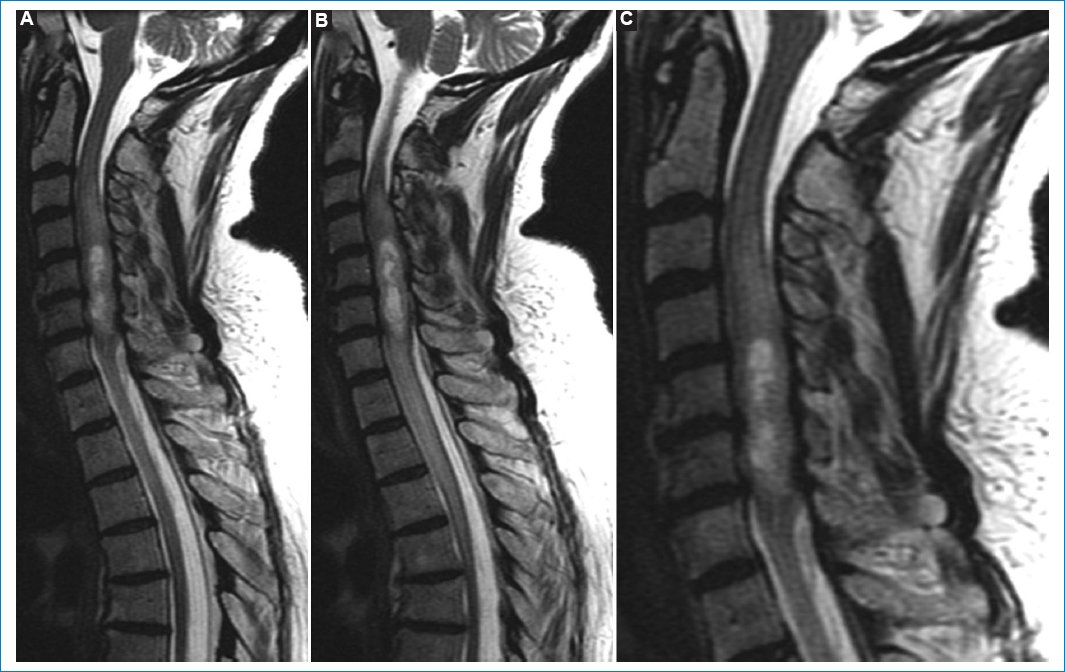

Resonancia magnética

Se aprecia un tumor intradural intramedular que tiene una extensión de cuatro vértebras, desde C3 a C6 (Figs. 14).

Figura 1. RM sagital ponderada en T2. Muestra aumento del tamaño de la médula espinal con centro de hiperintensidad intramedular difusa de extensión longitudinal, compatible con infiltración tumoral con centro quístico: cortes contiguos (A y B) y ampliación de A (C).

Tiene una posición central con una porción quística intratumoral. La lesión es isointensa en T1 e hiperintensa en T2 y STIR (Figs. 15). Después de administrar contraste paramagnético endovenoso hay realce periférico, especialmente alrededor de la formación quística. Por debajo del polo inferior se ve siringohidromielia de corto trayecto. Las características de las imágenes coinciden con las descripciones que aparecen en la bibliografía35.